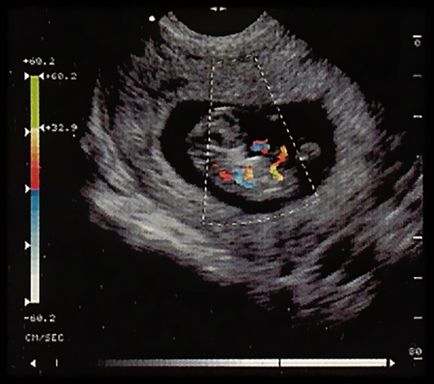

Imagini în modul Doppler color: se poate observa fluxul sanguin

Undele sonore sunt reflectate de obiecte în mișcare, echipament procesează semnalele recepționate și creează o imagine bidimensională multicoloră. Era doctorul o vede dacă există ceva greșit în modul în care sângele curge prin vasele. În ceea ce privește aplicațiile acestei tehnici, acestea sunt puține:

Este o metodă de scanare duplex include RDC sau Doppler color. Deci, ce este, cu ultrasunete RDC? Este tot aceeași ecografie, dar rata de diferite fluxul de sânge, marchează cu culori diferite. Ca urmare, imaginea rezultată toate vasele mari obține culoarea lor, poate fi văzut și starea rezervelor de sânge. Este acest proces necesită o senzori cu ultrasunete special configurate, și, de asemenea, permite să observe primele stadii de dezvoltare a tumorii.

fat folosind studiu de ultrasunete cu RDC

Aceasta tehnica este foarte eficient atunci când examinarea femeile gravide. Că RDC (inclusiv cu ultrasunete), se lasă să se afle mai mult pe douăzeci și treia săptămână de dezvoltare, nu se dezvoltă în cazul în care copilul lipsa de oxigen. Dacă se dovedește că răspunsul este pozitiv, medicul caută, ce fel de nave (în uter sau placenta) sunt responsabile pentru dezvoltarea patologiei, evaluează gradul de hipoxie copilului. Numai atunci se poate selecta un tratament adecvat: de prescriere plimbari mai frecvente, primirea de preparate speciale sau recomanda livrare devreme.

Doppler color fetale

Același lucru este valabil și pentru copil: fructul este studiat din toate părțile și în toate planurile, și în timp real. Specialistul poate vedea toate anomaliile, malformații. Mai ales eficientă această metodă este prezenta deformări faciale (cheiloschizis, palatoschizis si alte defecte), probleme in dezvoltarea membrelor. Mai mult decât atât, abaterea va fi văzută chiar și în stadii incipiente de dezvoltare. Pentru a obține date mai precise, metodologia CDM combinat cu ultrasunete tridimensional.